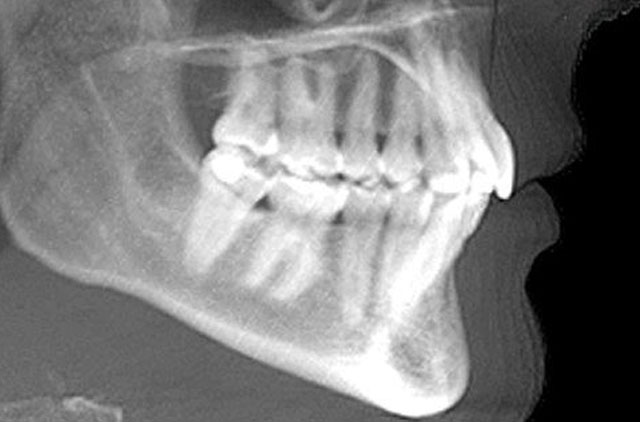

-Panoramica (OP)

-Panorámica (OP)

-Panorámica (OP) con 1.25 de Magnificación para implantes

-Panorámica Región Dientes Anteriores

-Panorámica Región Derecha

-Panorámica Región Izquierda